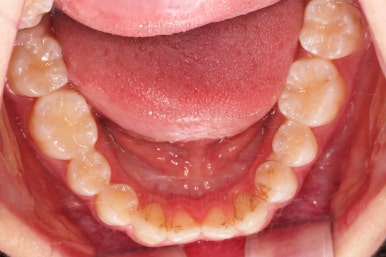

교합이 잘 맞아졌고요.

위아래 앞니도 서로 가까워졌어요.

치열도 가지런해졌고, 과개교합도 잘 개선이 되었습니다.

아래 앞니가 2개인 것이 표시가 안날 정도로 자연스럽게 교합이 맞아졌습니다.